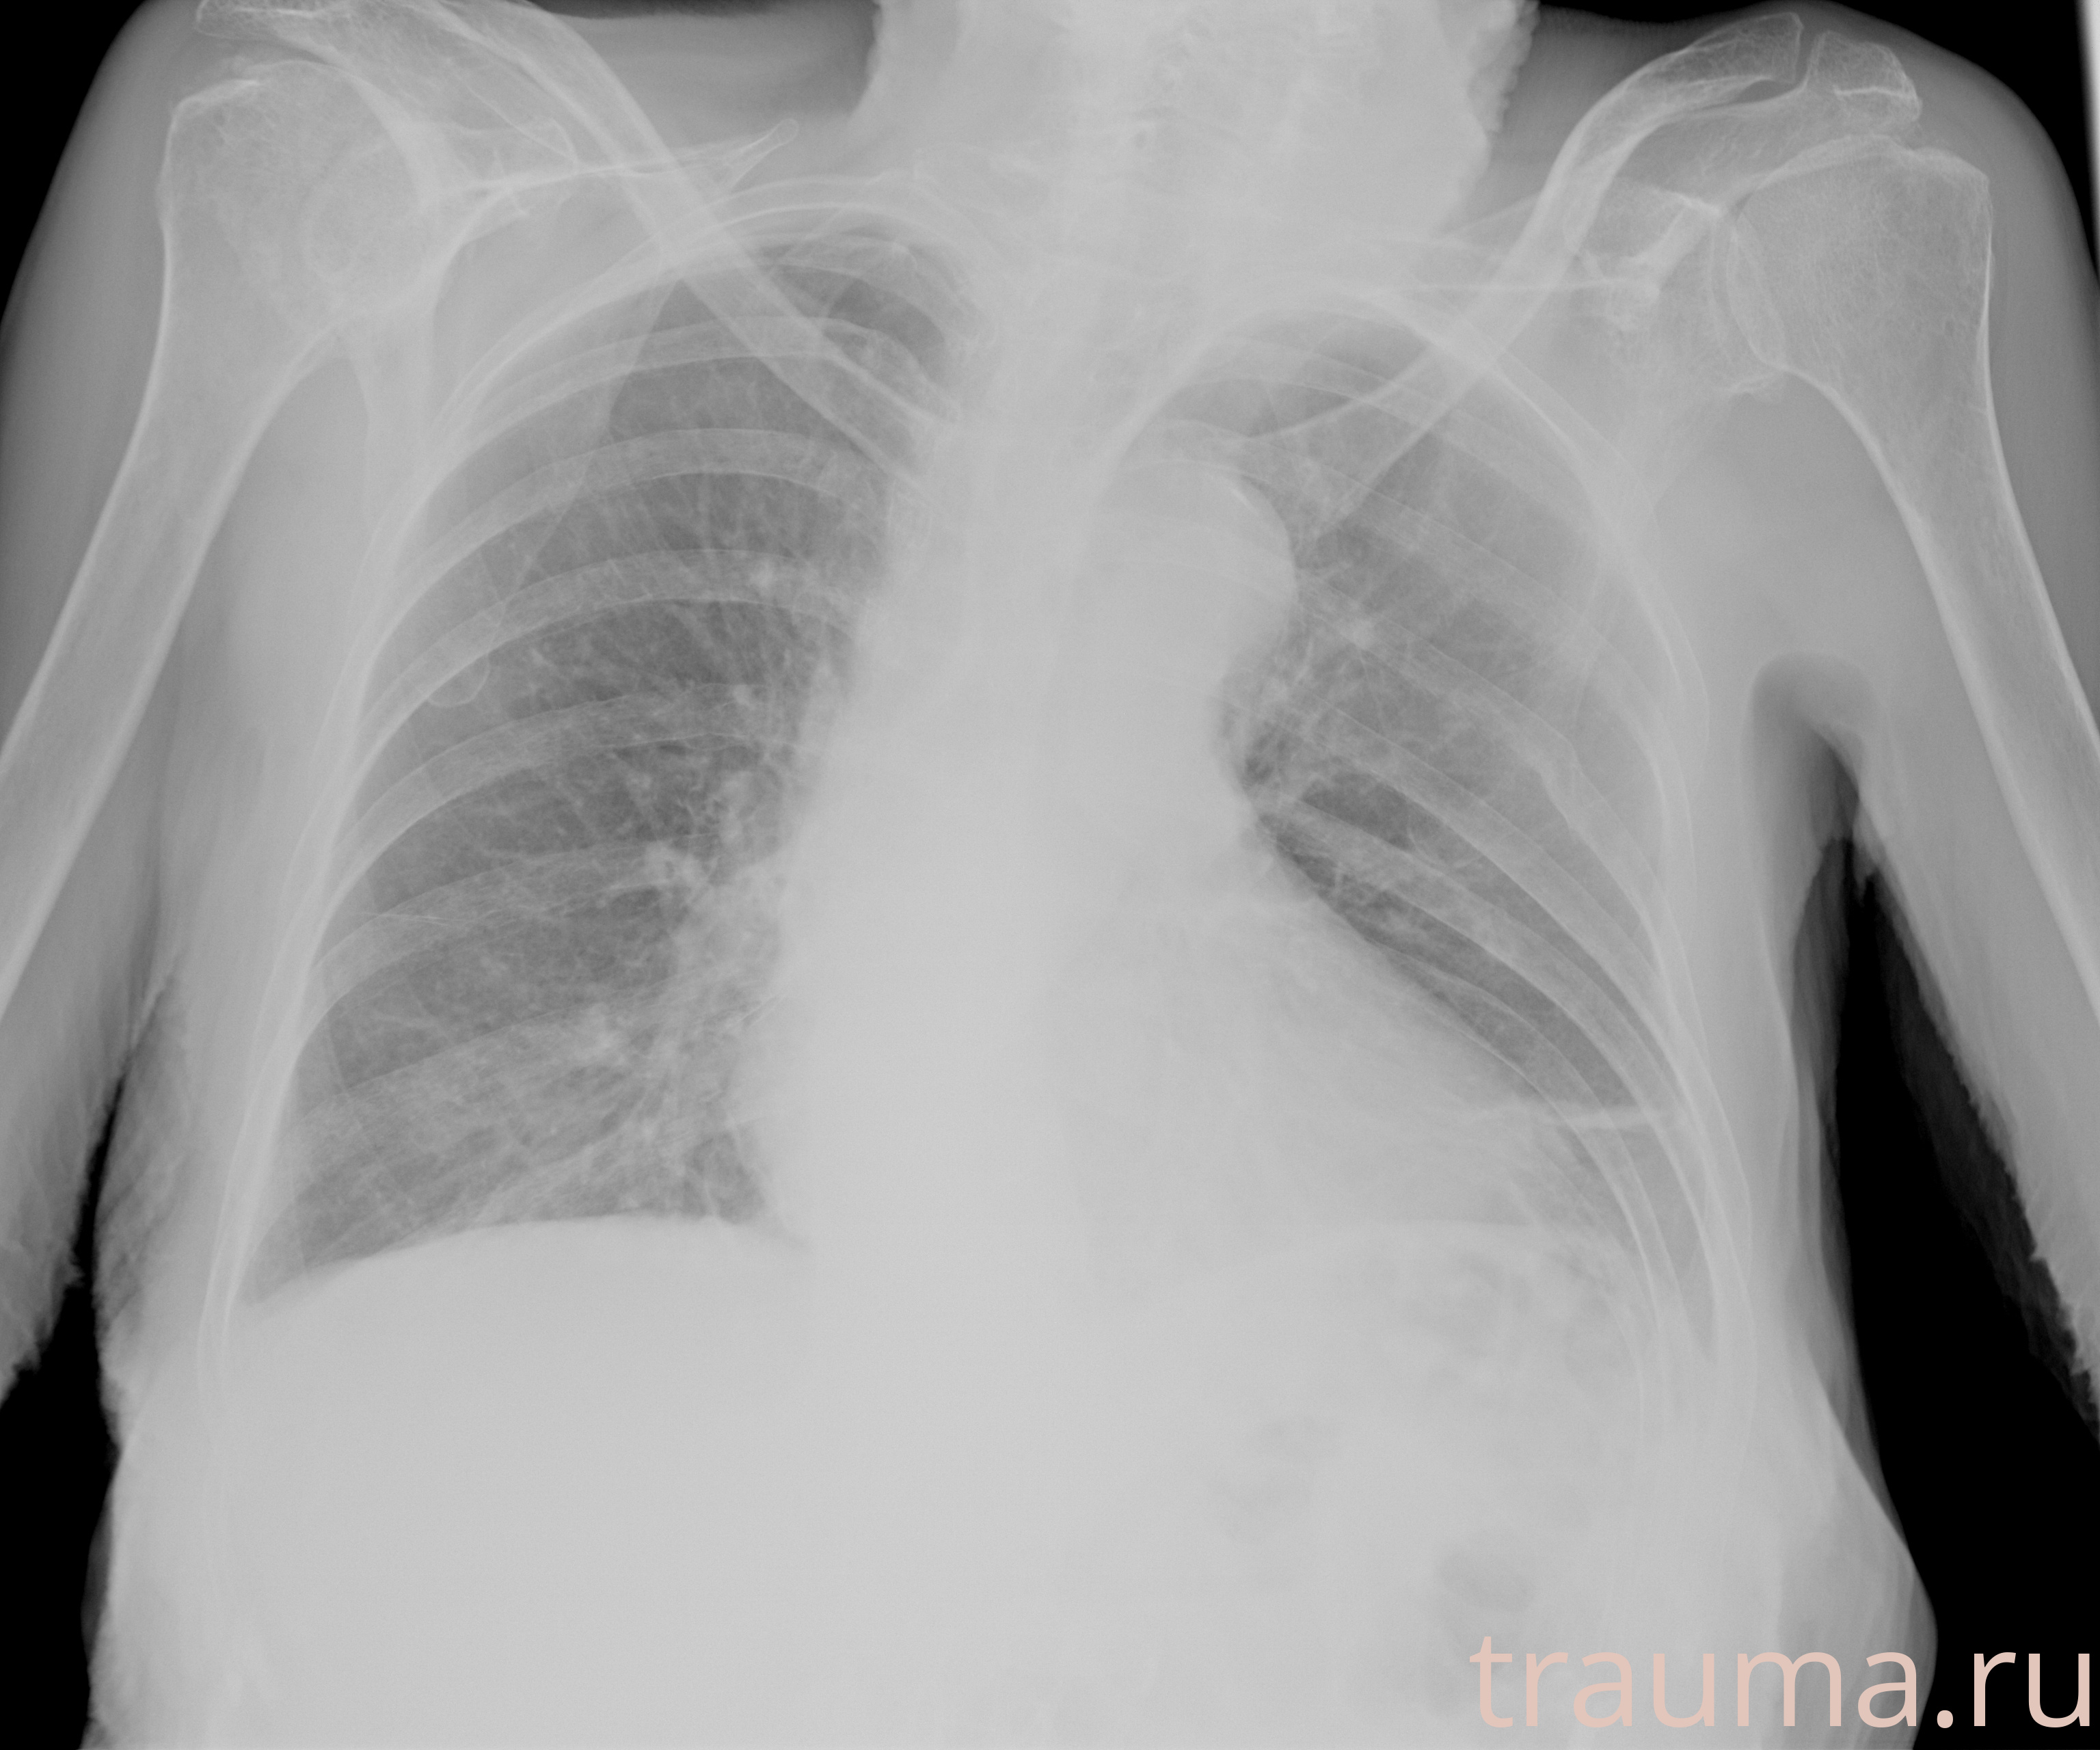

Рентгенограммы

Рентген на дому: по вашему адресу приезжает врач-рентгенолог, травматолог-ортопед с мобильным рентгеновским аппаратом, проводит диагностику травмы или заболевания, делает необходимые рентгенограммы, дает рекомендации по дальнейшему лечению. Получить качественные снимки в домашних условиях возможно благодаря уникальной методике, разработанной МосРентген Центром для института  Склифосовского

при переломе шейки бедра и пневмонии от компании МосРентген Центр - партнера Института имени Склифосовского